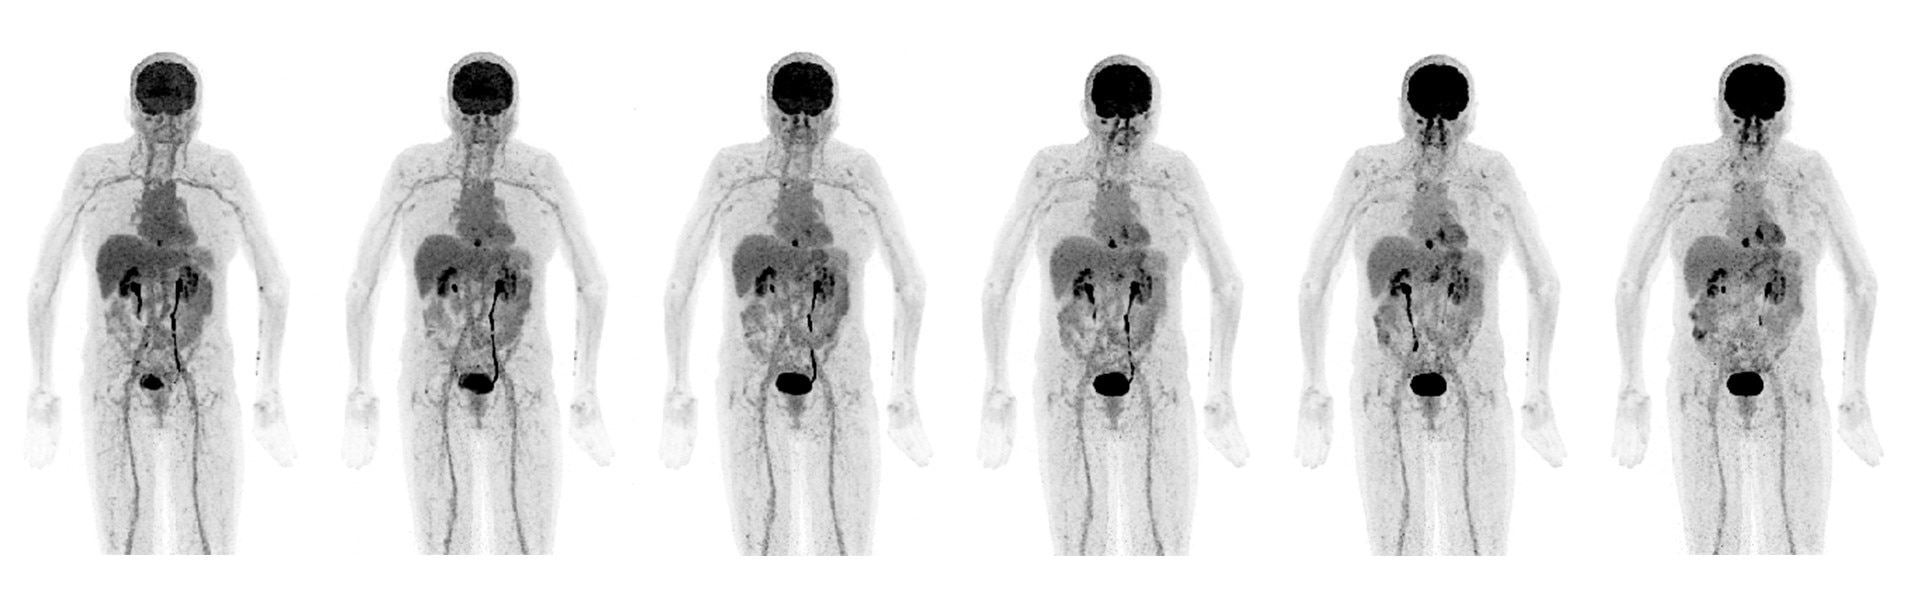

Imagens Clínicas

Várias lesões pequenas nas pernas e ao longo do pescoço.

A lesão da orelha direita mede na TC 3,5 mm. Tumor no quadril comendo o osso.

Cervical direito medindo 6 mm.

Acne visto nas costas.

Pulmão direito, virilha direita e tumor atrás do joelho direito.

Câncer na cabeça e pescoço.

Pós-radioterapia, progresso do câncer. Pequeno câncer de mama.

Linfonodos ávidos por FDG na axila esquerda (vacinação contra COVID-19).